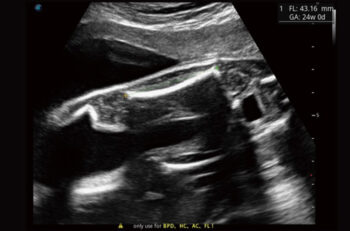

S-Fetus

Найдвартай том өгөгдлийн гүнзгий суралцах алгоритм дээр суурилсан S-Fetus бол стандарт план автоматаар олж авах, хэмжих гайхалтай шийдэл юм. Нэг товшилтоор ургийн биометрийн нийтлэг үр дүнг өндөр оюун ухаан, нарийвчлал, үр ашигтайгаар гаргаж, мэс заслын явцад урьд өмнө хэзээ ч байгаагүй хялбар байдалд хүрдэг.

Auto OB

Автомат OB нь ургийн биометрийг хурдан бөгөөд өндөр үр ашигтай болгодог. Үүний зэрэгцээ, гүнзгий суралцахад суурилсан энэхүү аргын илүү тогтвортой үр дүн нь хэрэглэгчээс хамааралтай хэлбэлзлийг үр дүнтэй бууруулж чадна.